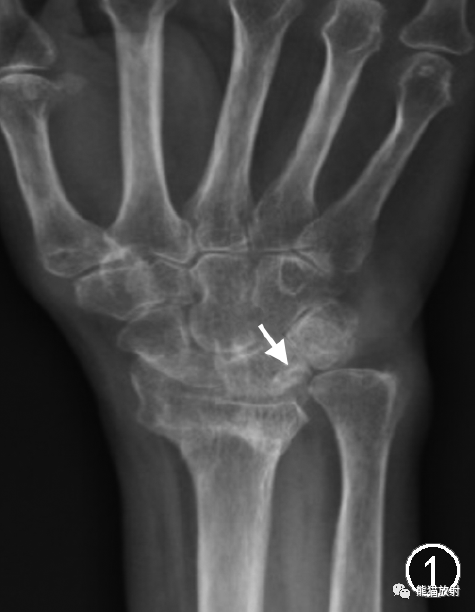

图1 继发于桡骨远端骨折畸形愈合的尺骨撞击综合征。女,66岁,右侧桡骨远端骨折愈合后右腕关节疼痛。腕关节X线正位片示桡骨远端骨折畸形愈合,继发尺骨相对过长、尺骨正向变异,月骨近端尺侧面骨质硬化改变(↑)

标准后前位(肩关节外展90°、肘关节屈曲90°、腕关节中立位)X线摄片的典型表现包括尺骨正向变异,偶尔可见尺骨中性变异或尺骨负向变异,以及导致尺骨相对过长或桡骨远端背倾程度增加的其他因素,例如桡骨远端骨折的畸形愈合(图1);月骨近端尺侧面、三角骨近端桡侧面及尺骨头关节面硬化和软骨下囊变(图1,2)。